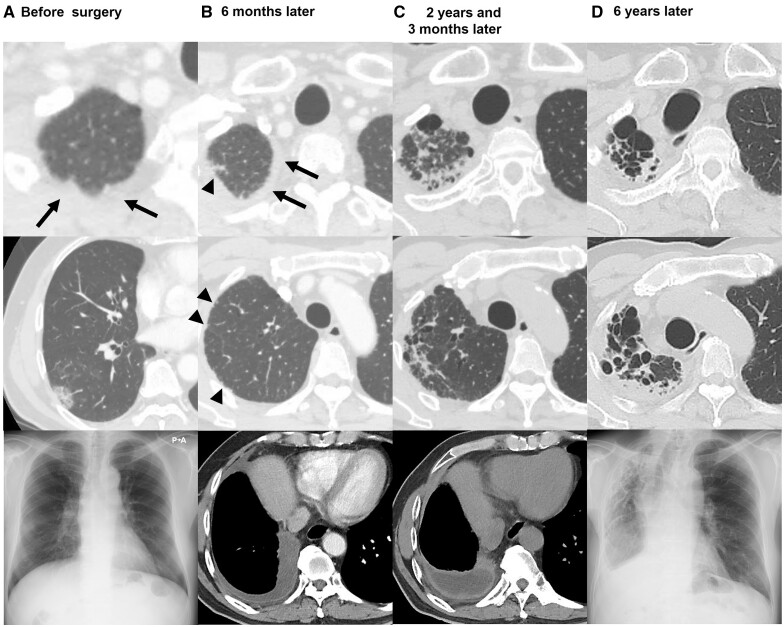

Results: Among the 587 included patients, 25 patients (4.3%) were diagnosed as unilateral upper-PF. The 3-, 5- and 10-year cumulative incidence of unilateral upper-PF was 2.3%, 3.3% and 5.3%, respectively. In multivariable analysis, male sex, presence of a pulmonary apical cap, lobar resection and low % vital capacity (%VC < 80%) were independent perioperative associated factors. The 10-year cumulative incidence was 6.3% in patients treated with lobar resection, 8.0% in male patients, 10.3% in patients with pulmonary apical cap and 14.5% in patients with low %VC. Postoperative pleural effusion at 6 months after surgery was much more common in the patients who later developed unilateral upper-PF (96.0% vs 24.2%). This pleural effusion persisted and was accompanied thereafter by pleural thickening and subpleural pulmonary fibrosis. During the clinical courses of 25 patients with unilateral upper-PF, 18 patients presented symptoms related to upper-PF and 6 patients died.

Conclusions: Unilateral upper-PF is an occasional but under-recognized late complication after lung cancer surgery.